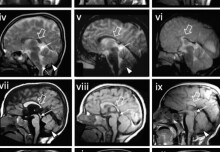

Molecular causes of rare neurological condition in children revealed

A new study has identified the molecular defects underlying a complex developmental brain condition in children.